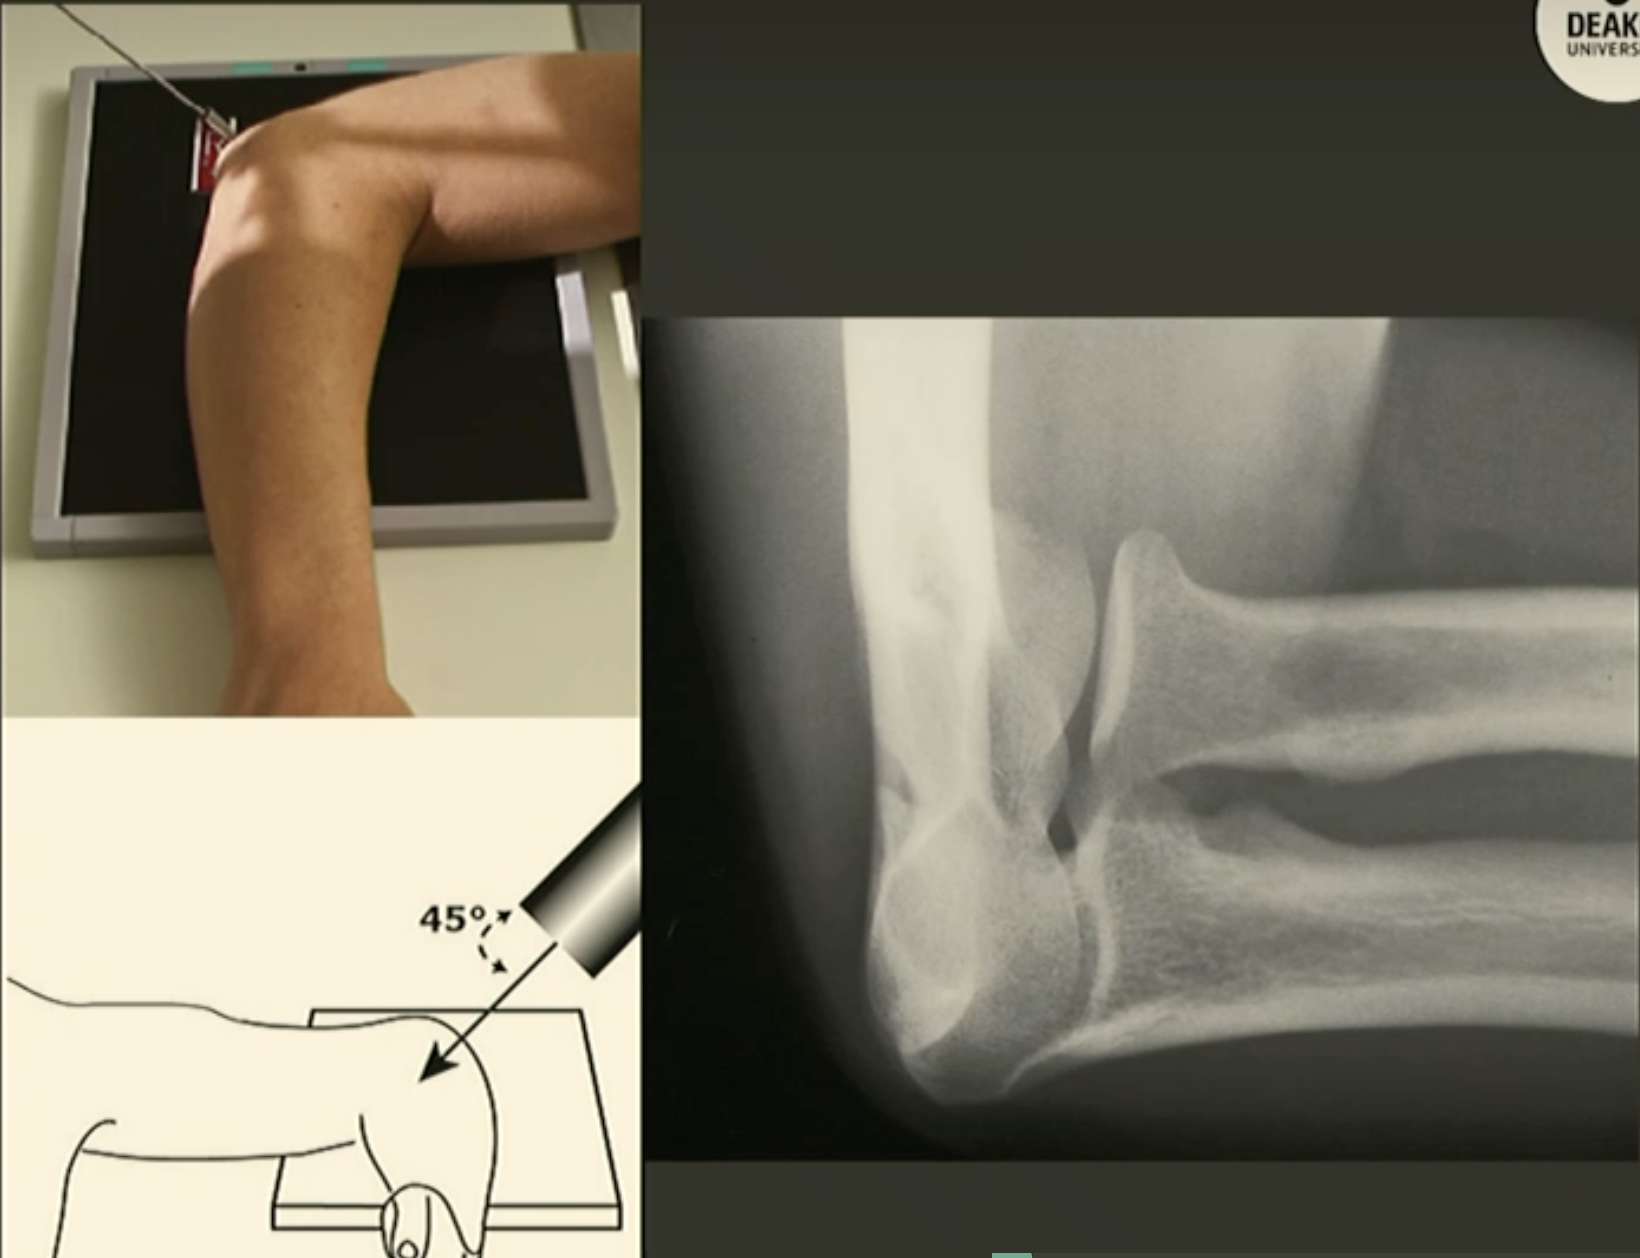

Coyle’s (Radial Head View) Elbow

Fine FS, 100cm

60kVp/3mAs

Tube angle 35-45 degrees towards humerus

CR: Radial head

Reverse Coyle’s Elbow

Tube angle 35-45 degrees away from humerus

CR: 1cm anterior to elbow joint